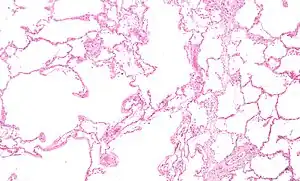

| Section of a lung showing centrilobular emphysema, with enlarged airspaces in the centre of a lobule usually caused by smoking and a major feature of COPD | |